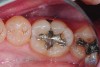

Fig 1. Excellent clinical condition of a 26-year-old Class II silver cermet restoration in a second permanent premolar tooth.

Figure 1

The properties that have challenged GICs as a bulk-fill material in the past are their lowered fracture strength and wear resistance and an opaque appearance. In spite of these negatives, even full-contour/monolithic applications of conventional GICs have performed much better than expected in durability when compared with amalgam and composites. For example, a recent study found no difference in the survival rates of single-surface and multiple-surface GICs and amalgam (primary and permanent teeth) after 6 years and 4 years, respectively.14 A 10-year clinical trial of high-viscosity GICs placed into permanent posterior teeth showed 86.5% of single-surface and 57.6% of multiples were still in service.15 Furthermore, a 2-year study comparing a packable composite versus a high-viscosity GIC showed very similar retention rates for both Class I and Class II restorations.16 Figure 1 shows a Class II, silver cermet restoration (Ketac™ Silver, 3M ESPE, www.3MESPE.com) from the author’s private practice that has been in clinical service for 26 years. Recently, a clinical technique in which a nanofilled light-cured resin glaze is applied to the surface of a high-viscosity GIC (EQUIA™ Fil and EQUIA™ Coat, GC America, www.gcamerica.com) has been found to significantly increase physical properties and durability of the final restoration.17,18 This coating is reported to penetrate 30 µ to 50 µ into the surface of the GIC and will last ≥ 6 months. The final GIC restoration can be recoated with the glaze periodically to extend the clinical benefit. Thus, if bulk-filling applications are desired, GICs may be superior to composite resins in many cases.